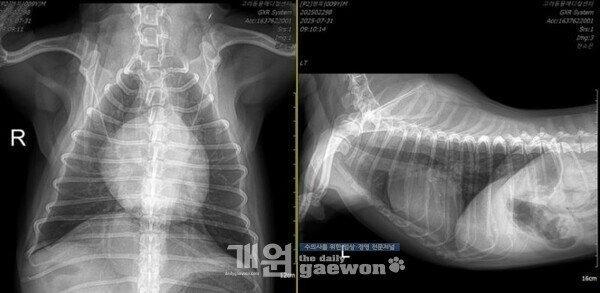

또 다른 환자의 흉부방사선이다.

이 환자는 2년간 피모벤단을 먹으면서 B2 로 관리받았고, 최근에 한 번의 폐수종이 있었는데, 그 이후로 퇴원이 안 되는 상황이었고, 고려 응급실로 밀고들어와서 투석부터 하고있다. 이뇨제는 신장수치때문에 더 쓸 수가 없고, 투석의 초여과 기능을 통해 폐의 물을 뺐다.